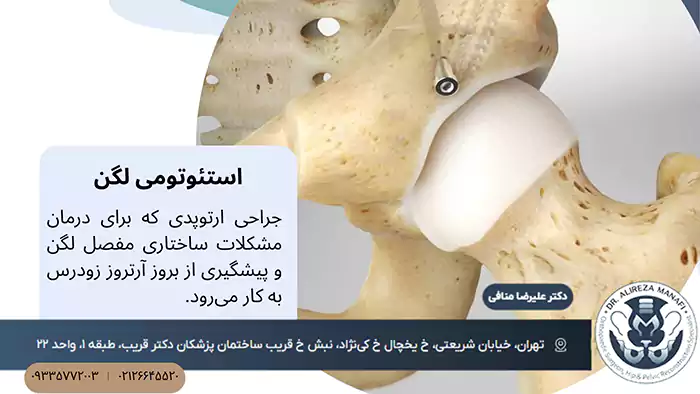

استئوتومی لگن یک روش جراحی ارتوپدی پیشرفته است که برای درمان مشکلات ساختاری مفصل لگن و پیشگیری از بروز آرتروز زودرس به کار میرود. بسیاری از بیماران جوانی که دچار دیسپلازی لگن یا مشکلات مادرزادی و اکتسابی در این ناحیه هستند، با کمک این جراحی میتوانند سالهای طولانی از مفصل طبیعی خود استفاده کنند، بدون اینکه به تعویض مفصل نیاز داشته باشند.

استئوتومی لگن در واقع نوعی جراحی اصلاحی استخوان است که هدف اصلی آن تغییر زاویه و موقعیت استخوان لگن برای بهبود عملکرد مفصل ران است. در افراد سالم، حفره لگن یا همان استابولوم، سر استخوان ران را به صورت کامل و صحیح در بر میگیرد و باعث میشود فشارها به صورت طبیعی توزیع شوند. اما در برخی افراد به دلایل مادرزادی یا رشد غیرطبیعی، این حفره عمق کافی ندارد و سر استخوان ران به درستی در جای خود قرار نمیگیرد.

همین وضعیت باعث افزایش اصطکاک، ساییدگی غضروف و در نهایت بروز درد و محدودیت حرکتی میشود. در چنین شرایطی، جراح به جای اینکه کل مفصل را با یک پروتز مصنوعی جایگزین کند، استخوان لگن را برش داده و دوباره در زاویهای جدید ثابت میکند تا تماس مناسبتری با سر استخوان ران ایجاد شود.